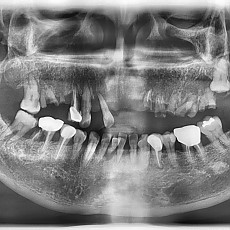

시술전후사진 2 페이지

Total 62건 2 페이지